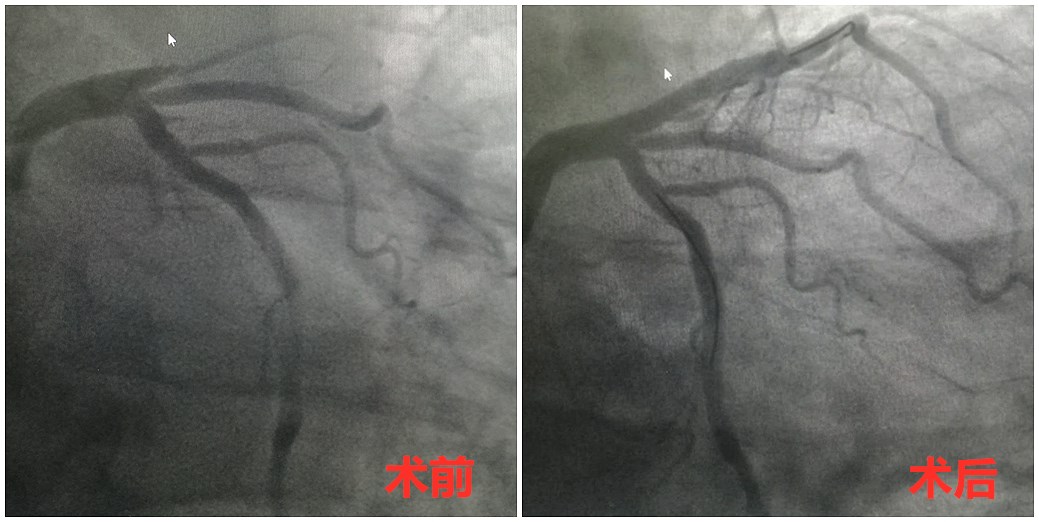

转运途中,120团队快速做好术前准备及术前沟通谈话。14:25,载着老张的急救车抵达玉环市人民医院,老张被直接送入介入导管室。14:28,等候多时的心内科介入团队火速为老张开展心脏支架植入术。术中,心内科主任阮宏标发现老张血管畸形,手术难度系数骤增。危急时刻,他带领团队冷静应对,最终于15:23成功开通闭塞血管。

从进入医院到手术开始,短短3分钟,“双绕行”的救心高速路,不设“中间站”,全程无挂号、缴费、办住院等程序,再为生命赢转机。而在血管畸形的困境面前,从进医院大门到闭塞的血管开通,玉环市人民医院心内科介入团队也仅用时58分钟,大大低于入院到手术干预的90分钟国际标准。